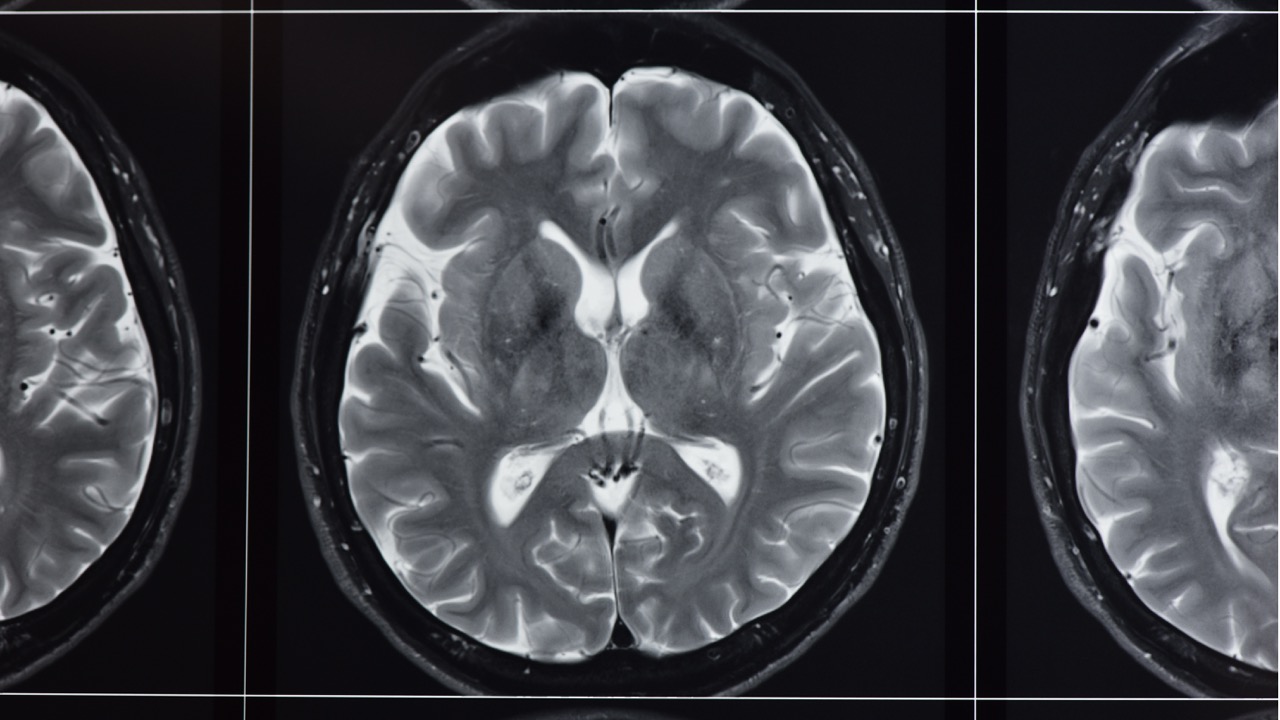

Precision MRI is expanding its neurological imaging capabilities with the addition of Diffusion Tensor Imaging (DTI) brain scans an advanced MRI technique increasingly used to evaluate traumatic brain injury, stroke, neurodegenerative disease, and complex neurological symptoms that often go undetected on standard MRI.

When to Get a DTI Brain Scan After a Car Accident: Signs to Watch You walked away from the accident.